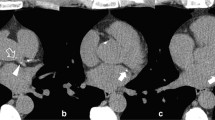

•• Lin A, Manral N, McElhinney P, Killekar A, Matsumoto H, Kwiecinski J, et al. Deep learning-enabled coronary CT angiography for plaque and stenosis quantification and cardiac risk prediction: an international multicentre study. Lancet Digit Health. 2022;4:e256–65. Findings from this study showed that a deep learning network can be applied to rapidly segment and characterize coronary plaque from coronary CT angiography; with AI-enabled measurement of total plaque volume predicting future heart attack in the multicenter SCOT-HEART trial.